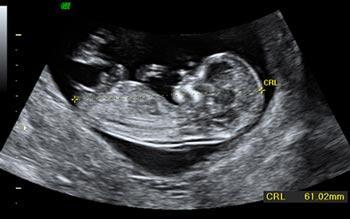

Ecografía del tercer trimestre.

Esta es la última semana en la que te pueden hacer la última ecografía de tu embarazo, normalmente se hace entre la 30 y la 34 semanas del embarazo, se trata de una ecografía

Con esta prueba los médicos se aseguraran que todo va correctamente cuando aun tienen tiempo para modificar algún problema que puedan observar antes del parto.